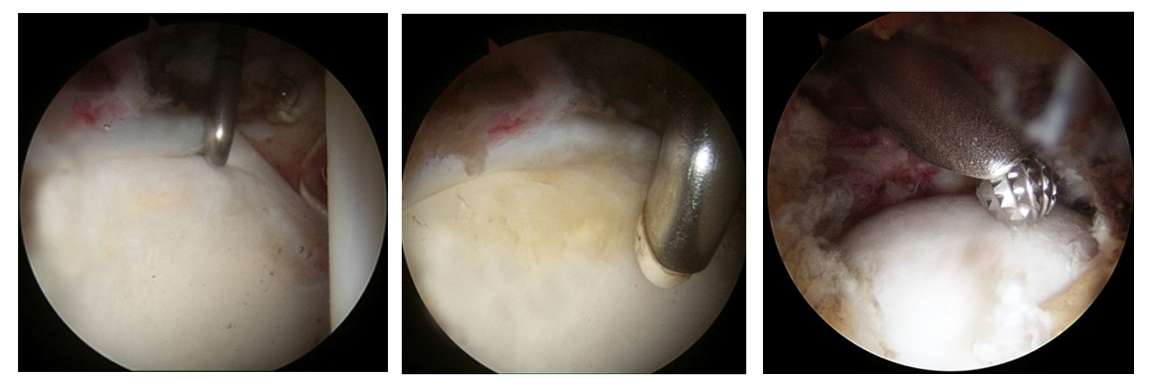

L'intervento chirurgico artroscopico, previa accurata valutazione clinico-strumentale, prevede la correzione della deformità ossea (fig. 4) mediante procedure minimamente invasive e mira a diminuire il rischio di sviluppare un'artrosi secondaria precoce e ad alleviare la sintomatologia presente.

Nelle lesioni del labrum acetabolare è interessata la struttura fibrocartilaginea ad anello fissata al bordo del cotile. Il labrum può essere parzialmente danneggiato o lesionato nella sua intera superficie. Le lesioni sono spesso associate al conflitto femoro-acetabolare, ma possono anche essere isolate (natura traumatica o degenerativa). L'artroscopia d'anca permette la riparazione di tali lesioni fissando il labbro all'osso del cotile mediante il posizionamento di ancorette e punti di tensionamento (fig. 5).

Le lesioni cartilaginee interessano la cartilagine di rivestimento delle superfici articolari (fig. 6) e possono derivare da diverse condizioni patologiche (traumi, FAI non trattato, osteonecrosi etc.). L'artroscopia permette di valutarne l'estensione in maniera più accurata rispetto alla diagnostica per immagini e, in caso di lesioni non troppo estese, l'esecuzione di procedure mirate alla rigenerazione della cartilagine articolare.